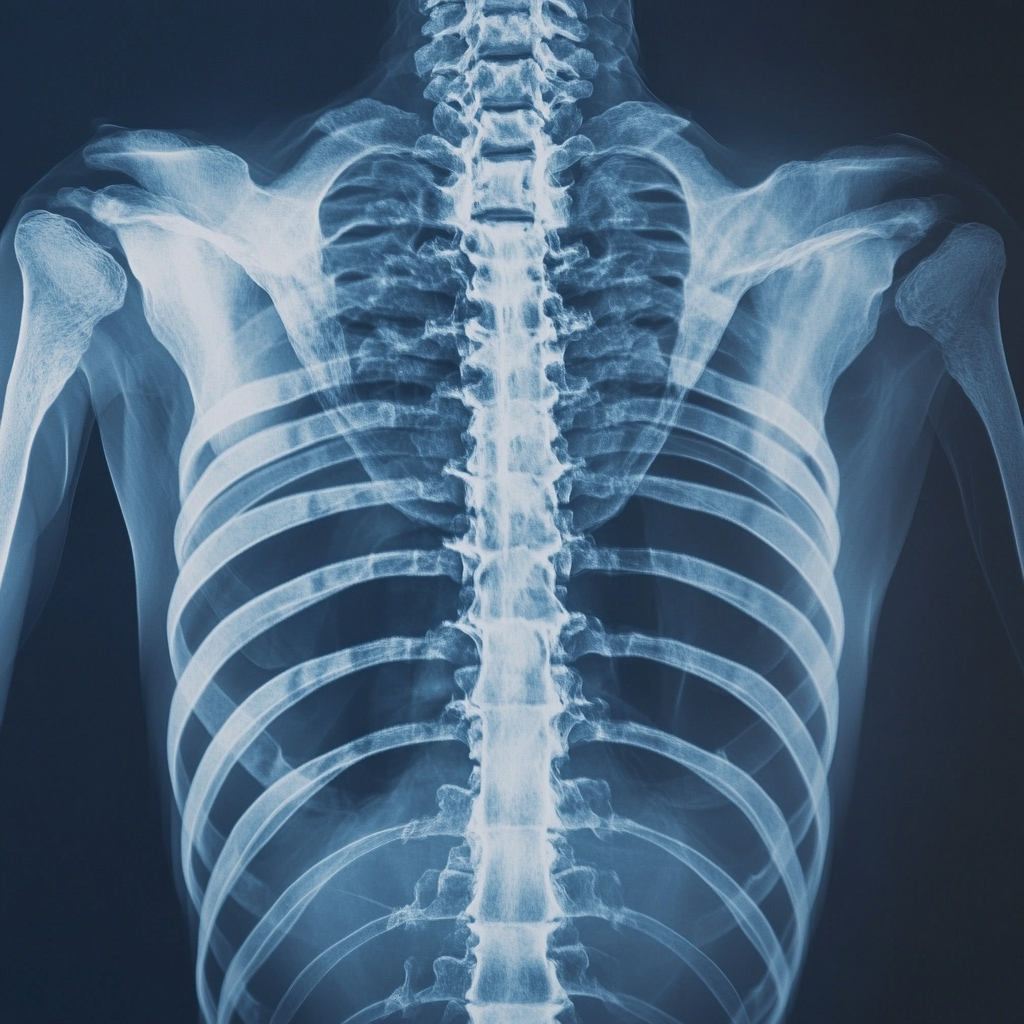

5. 골밀도 검사 🦴

골밀도 검사는 골다공증 위험을 평가하는 검사입니다. 폐경기 여성이나 노년층은 정기적으로 검사하는 것이 좋습니다. 골밀도가 낮을 경우 골절 위험이 높아질 수 있으며, 칼슘과 비타민 D 섭취, 규칙적인 운동을 통한 관리가 필요합니다.

| 골밀도 | T-점수 -1 이상 | 낮으면 골다공증 위험 |